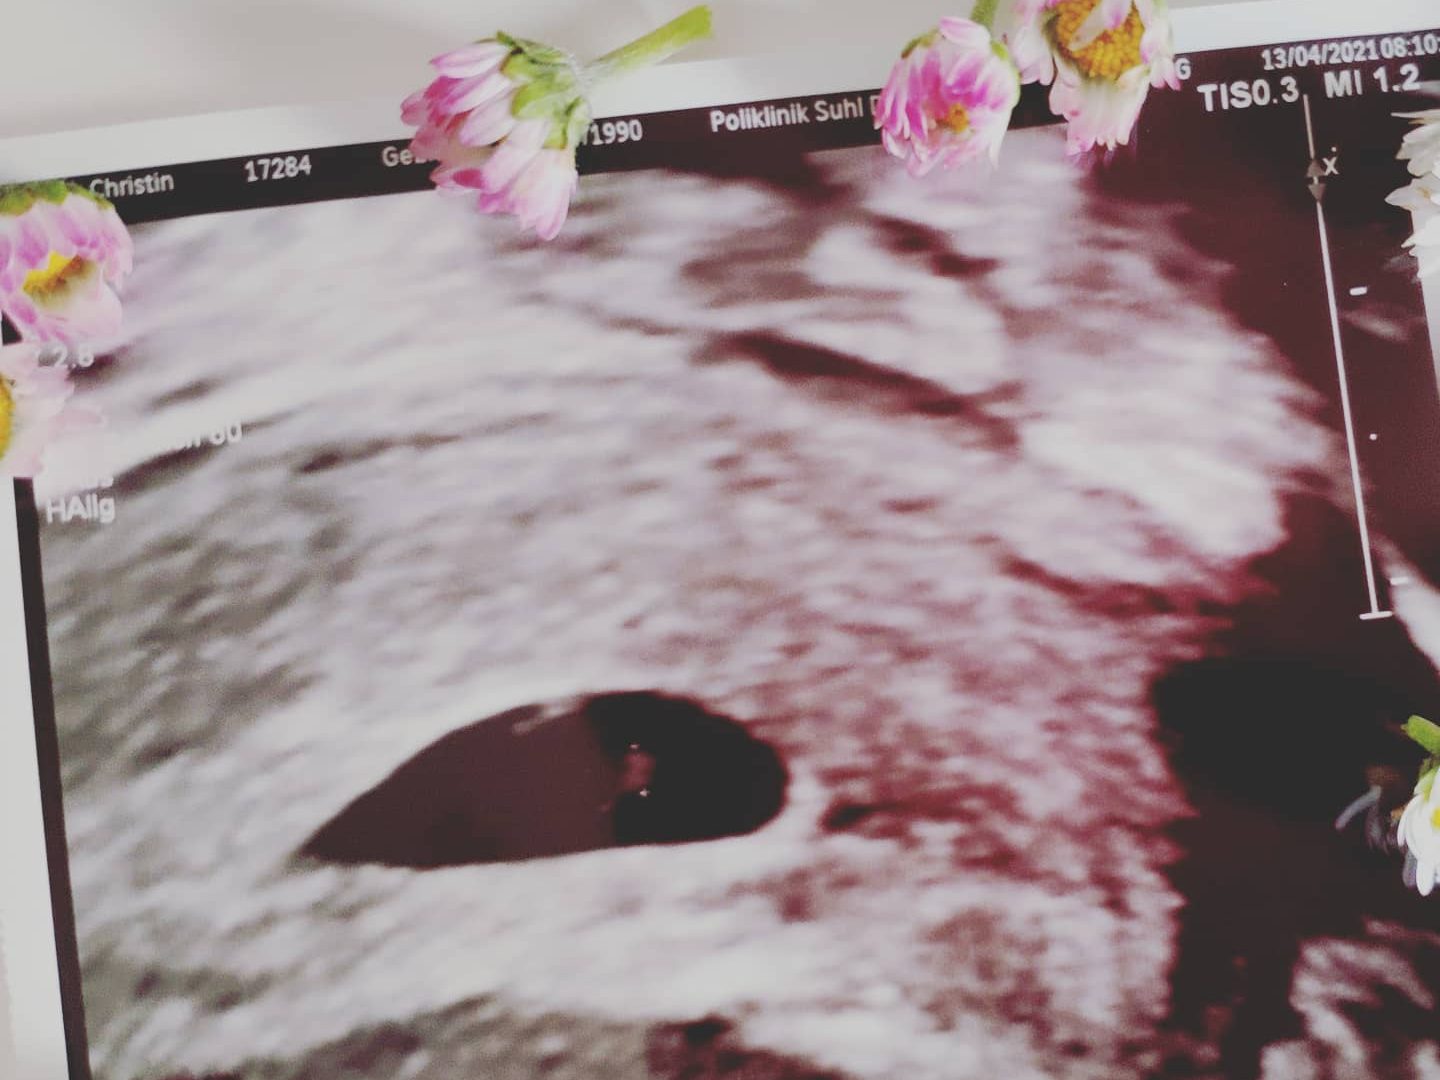

Wäre ich heute nochmal schwanger (und bis vor Kurzem war ich das ja sogar) oder hätte den Wunsch danach, würde ich sofort meine Ernährung umstellen, würde Mikronährstoffe zuführen, sehr auf mein Trinkverhalten achten (also viel Wasser), meinen Stress maximal reduzieren und mir, anstatt Panik zu schieben, ganz viel Vorfreude auf den kleinen Krümel in meinem Bauch erlauben. Ja, ich habe ein paar körperliche Defizite und ja, wenn ich in Bücher schaue, sehe ich lange Listen, die mir zeigen, wie schwer es werden wird. Aber ich sehe meine beiden Kinder und denke: Scheiß drauf. Wenn ich will, dann geht es auch. Basta!